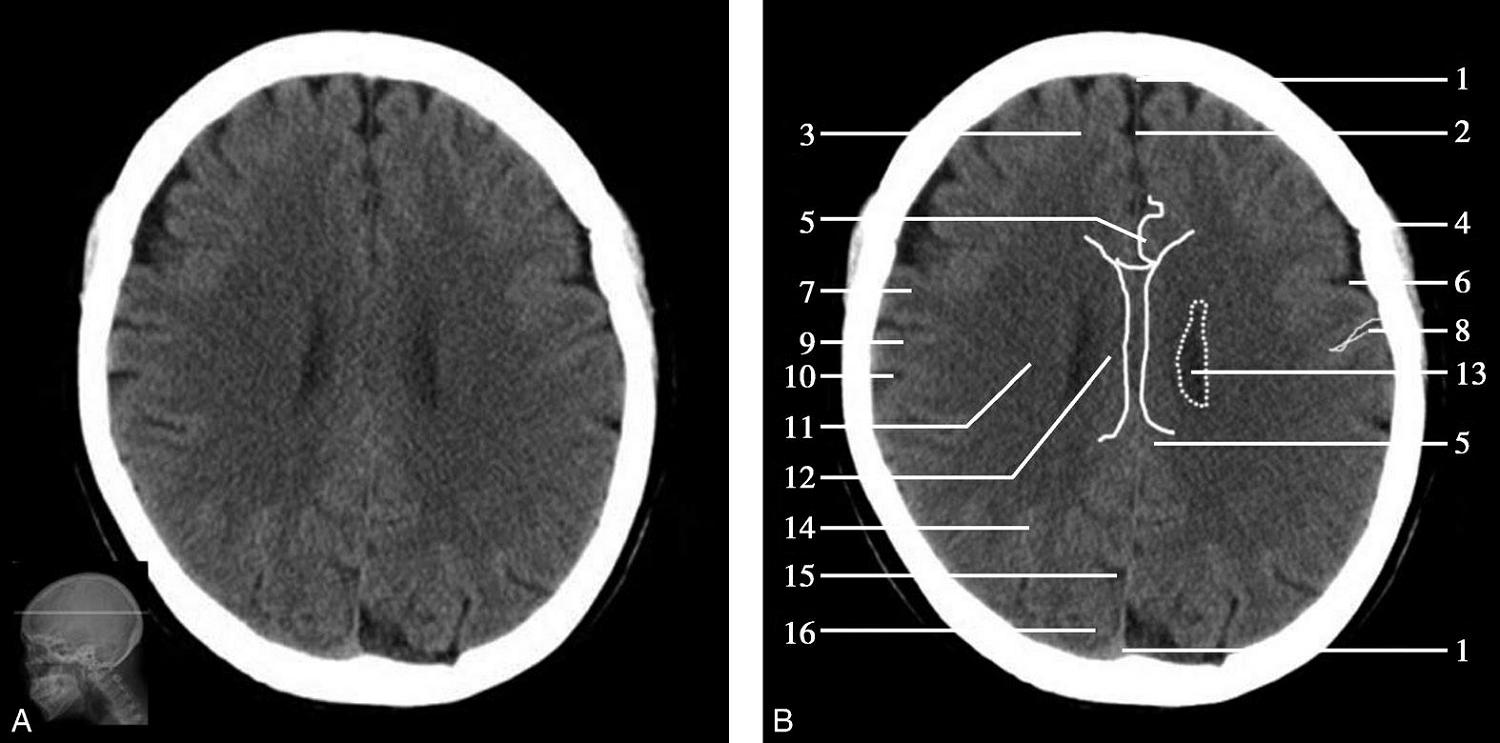

重要结构:中脑导水管、第三脑室、外侧裂池、岛叶、上矢状窦、四叠体池(图1-2-21~图1-2-23)。

图1-2-21 中脑导水管层面

A.横断面;B.横断面标注

1.额窦;2.上矢状窦;3.大脑镰;4.额叶;5.颞肌;6.外侧裂;7.岛叶;8.尾状核头;9.外囊;10.第三脑室;11.豆状核;12.颞叶;13.中脑;14.中脑导水管;15.环池;16.四叠体池;17.小脑上蚓部;18.枕叶

中脑位居此层面的中央,其腹侧可见两侧大脑脚,大脑脚底有黑质与红核,中脑背侧可见左右稍隆起者为上丘,上丘后方为四叠体池,中脑顶盖的前方可见中脑导水管断面呈针孔样,中脑外侧为环池,中脑前方中间为第三脑室下部。第三脑室下部两前外侧有尾状核头及豆状核壳部,尾状核头及壳核部分相连,壳核的外侧为屏状核、岛叶及外侧裂池,再外侧为颞盖,其前部为颞上回,后部为颞中回。外侧裂池分隔前方的额叶和后方的颞叶,可作为区分额叶与颞叶的重要标志。四叠体池后方有小脑上蚓及两侧呈倒“八”字形的小脑天幕,天幕后方为直窦和上矢状窦。